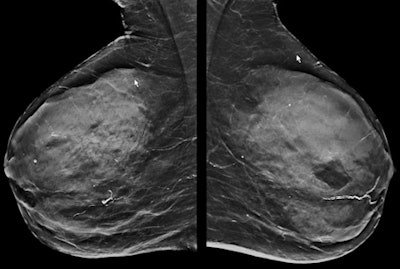

In particular, certain kinds of lesions are associated with an increased risk of breast cancer. Atypical ductal hyperplasia is associated with a 40% increased risk of breast cancer, and lobular intraepithelial neoplasia and flat epithelial atypia are both associated with a 21% increased risk. These lesions are treated with intensified surveillance and possibly tamoxifen, so while they may be called false positives on MRI, they are not completely harmless, even though they are still categorized as benign, added Kuhl, who is a keen advocate of abbreviated breast MRI studies (see images above).